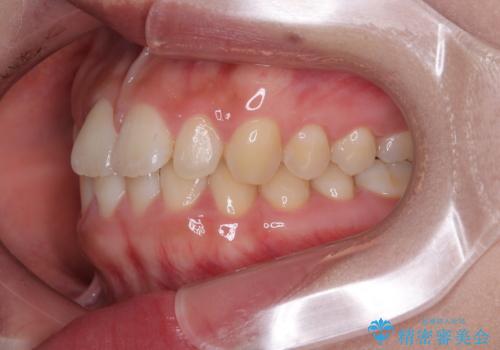

- 前歯のデコボコが気になるでのことで来院された患者様です。

歯列アーチが狭くスペース不足により前歯がデコボコしている状態でした。見た目を改善しつつ、前歯を前方に突出させず、自然な笑顔を目指したいというご希望でした。